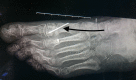

Figure 3. The distal chevron osteotomy and Kirschner (K)-wire fixation.

Black arrow showing the Kirschner wire fixation of the distal metatarsal chevron osteotomy.